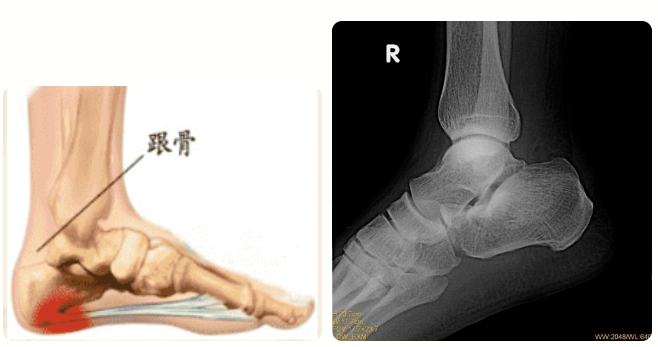

跟骨骨折后该怎么护理呢?市第五医院手足外科教你几个小妙招